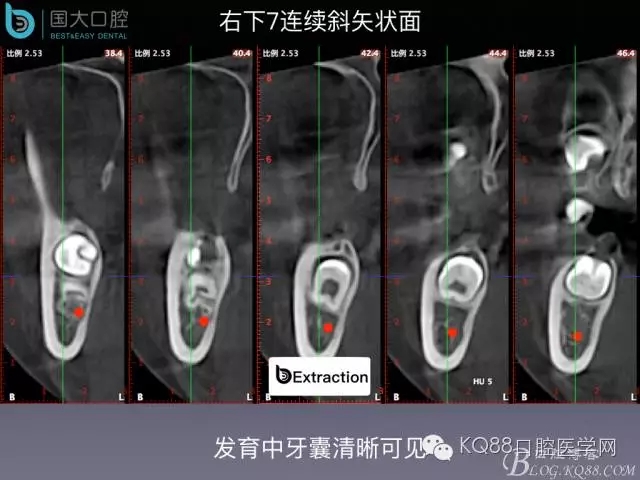

阻生牙的預(yù)防性拔除

- 牙齒拔除適應(yīng)證及第二磨牙遠中齲病